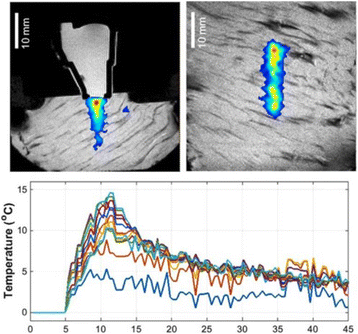

MRI image of applicator in pork muscle (axial section) after 7s showing thermal profile, and calculated temperature rise